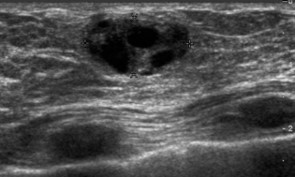

Images 1-3 below show the grossly varied appearances of galactocoele on ultrasound. All three of the following ultrasound images are lesions that were diagnosed as a galactocele after the aspiration.

Image 3